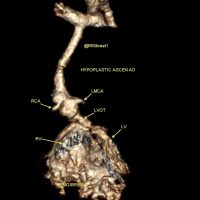

0Neonate with such HLHS Hypoplastic LV, LVOT & AORTA Ductus dependent systemic circulation. [gallery ids="18820,18823"] Mohamed Gibreel , FEBR (Fellowship of Egyptian Board of Radiology ) Cardiac imaging consultant at..